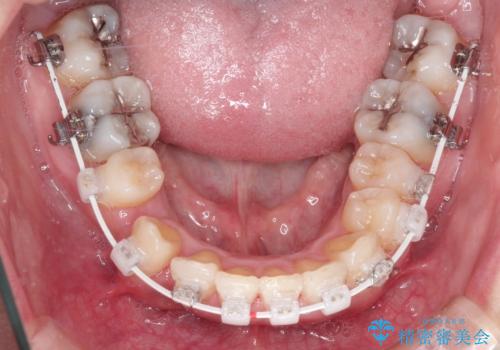

犬歯が変な位置にある 抜歯矯正により正しい位置へ

左上の犬歯が通常の位置より、かなり上方にあり、乳歯の残存と前歯のがたつきがありました。

残った乳歯と上下左右の永久歯を1本ずつ抜歯して、ワイヤーにて矯正することとしました。

犬歯も通常の位置にまで移動することができ、口元もすっきりすることができました。